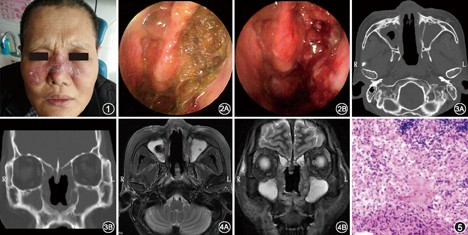

患者男,50岁,因"双侧鼻腔干燥伴涕中带血2年,加重伴面部皮疹3个月"于2016年11月5日入院。患者2年前无明显诱因出现双侧鼻腔干燥,伴涕中带血,为鲜血,量不多,无明显鼻塞、鼻痛,无发热、盗汗、潮红,无头痛、头晕,无咳嗽、咳痰,无眼痛、复视、视力下降,无耳鸣、听力下降,未予重视。3个月前患者自觉鼻部症状加重,伴流脓涕、嗅觉下降,发现面部散在丘疹,色红,有压痛,随后皮损面积扩大并融合成红褐色斑块,摩擦后表面有溃破,伴脓性分泌物流出。曾于外院就诊,给予中西医结合治疗(具体不详)及面部抗生素软膏涂抹,疗效欠佳,为进一步治疗来我院。查体:体温36.5℃,脉率76次/分,呼吸18次/分,血压107/78 mmHg(1 mmHg=0.133 kPa)。外鼻无畸形,皮肤丘疹自鼻根部向两侧蔓延,呈地图样,表面有溃破,可见脓性分泌物,表面有黄褐色污秽物附着(图1)。鼻前庭皮肤红肿,鼻毛脱落。鼻中隔大穿孔,鼻腔黏膜充血,双侧中鼻道及嗅裂见脓性分泌物,双侧下鼻甲及中鼻甲破坏,鼻中隔及鼻甲后端可见溃疡样新生物,周围黏膜组织充血、水肿(图2),双侧鼻窦区无明显压痛。悬雍垂缺失,软腭见瘢痕。入院诊断:鼻肿物;鼻中隔穿孔;面部皮疹。入院后完善血常规、生化检查,均未见明显异常;取皮肤分泌物做细菌培养,结果为金黄色葡萄球菌。给予抗生素软膏涂抹,疗效欠佳,后请皮肤科、呼吸内科等相关科室会诊,完善如下相关检查。T细胞斑点试验,检查结果为抗体A:53 SFCs/2.5E5 PBMC;抗体B:56 SFCs/2.5E5 PBMC[正常参考范围:(抗体A+抗体B)<6 SFCs/2.5E5 PBMC,若≥6 SFCs/2.5E5 PBMC则提示存在结核感染]。鼻窦CT平扫示:双侧上颌窦、筛窦、额窦、蝶窦内软组织密度影填充,窦壁骨质硬化,鼻中隔后端、双侧中下鼻甲骨质破坏(图3)。鼻窦MRI平扫示:全组鼻窦内长T1长T2信号影,鼻中隔后端、双侧中上鼻甲缺如,鼻骨及邻近双侧面颊部皮下软组织增厚,呈片状长T2信号影,鼻内病损与皮肤及皮下病损有连续性(图4)。胸部CT平扫示:骨性胸廓对称,纵隔、气管居中。双肺纹理稍粗,未见明显结节影,纵隔内未见肿大淋巴结影,心影未见异常。鼻内镜下取鼻腔内病损送病理,可见朗格汉斯巨细胞,周围有较为致密的淋巴细胞浸润,考虑结核结节(图5)。患者鼻结核诊断明确,后转入传染病医院就诊,给予患者异烟肼300 mg、利福平450 mg、乙胺丁醇750 mg每天1次口服三联抗结核治疗。2个月后回院复查皮疹减轻,遗留色素沉着及瘢痕。拟继续上述治疗4个月。